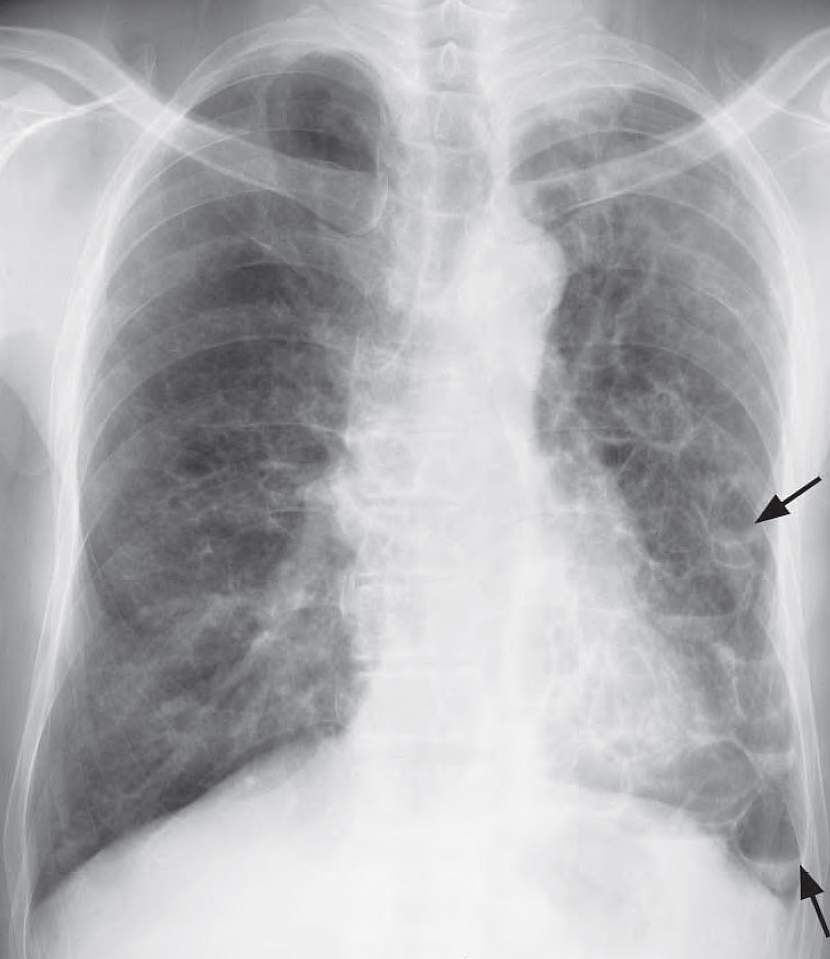

Frontal chest radiograph showing clusters of cystic spaces containing air-fluid levels (arrows) in the left mid and lower zones due to retained secretions in dilated bronchioles in bronchiectasis.

Diagnosis: Bronchiectasis